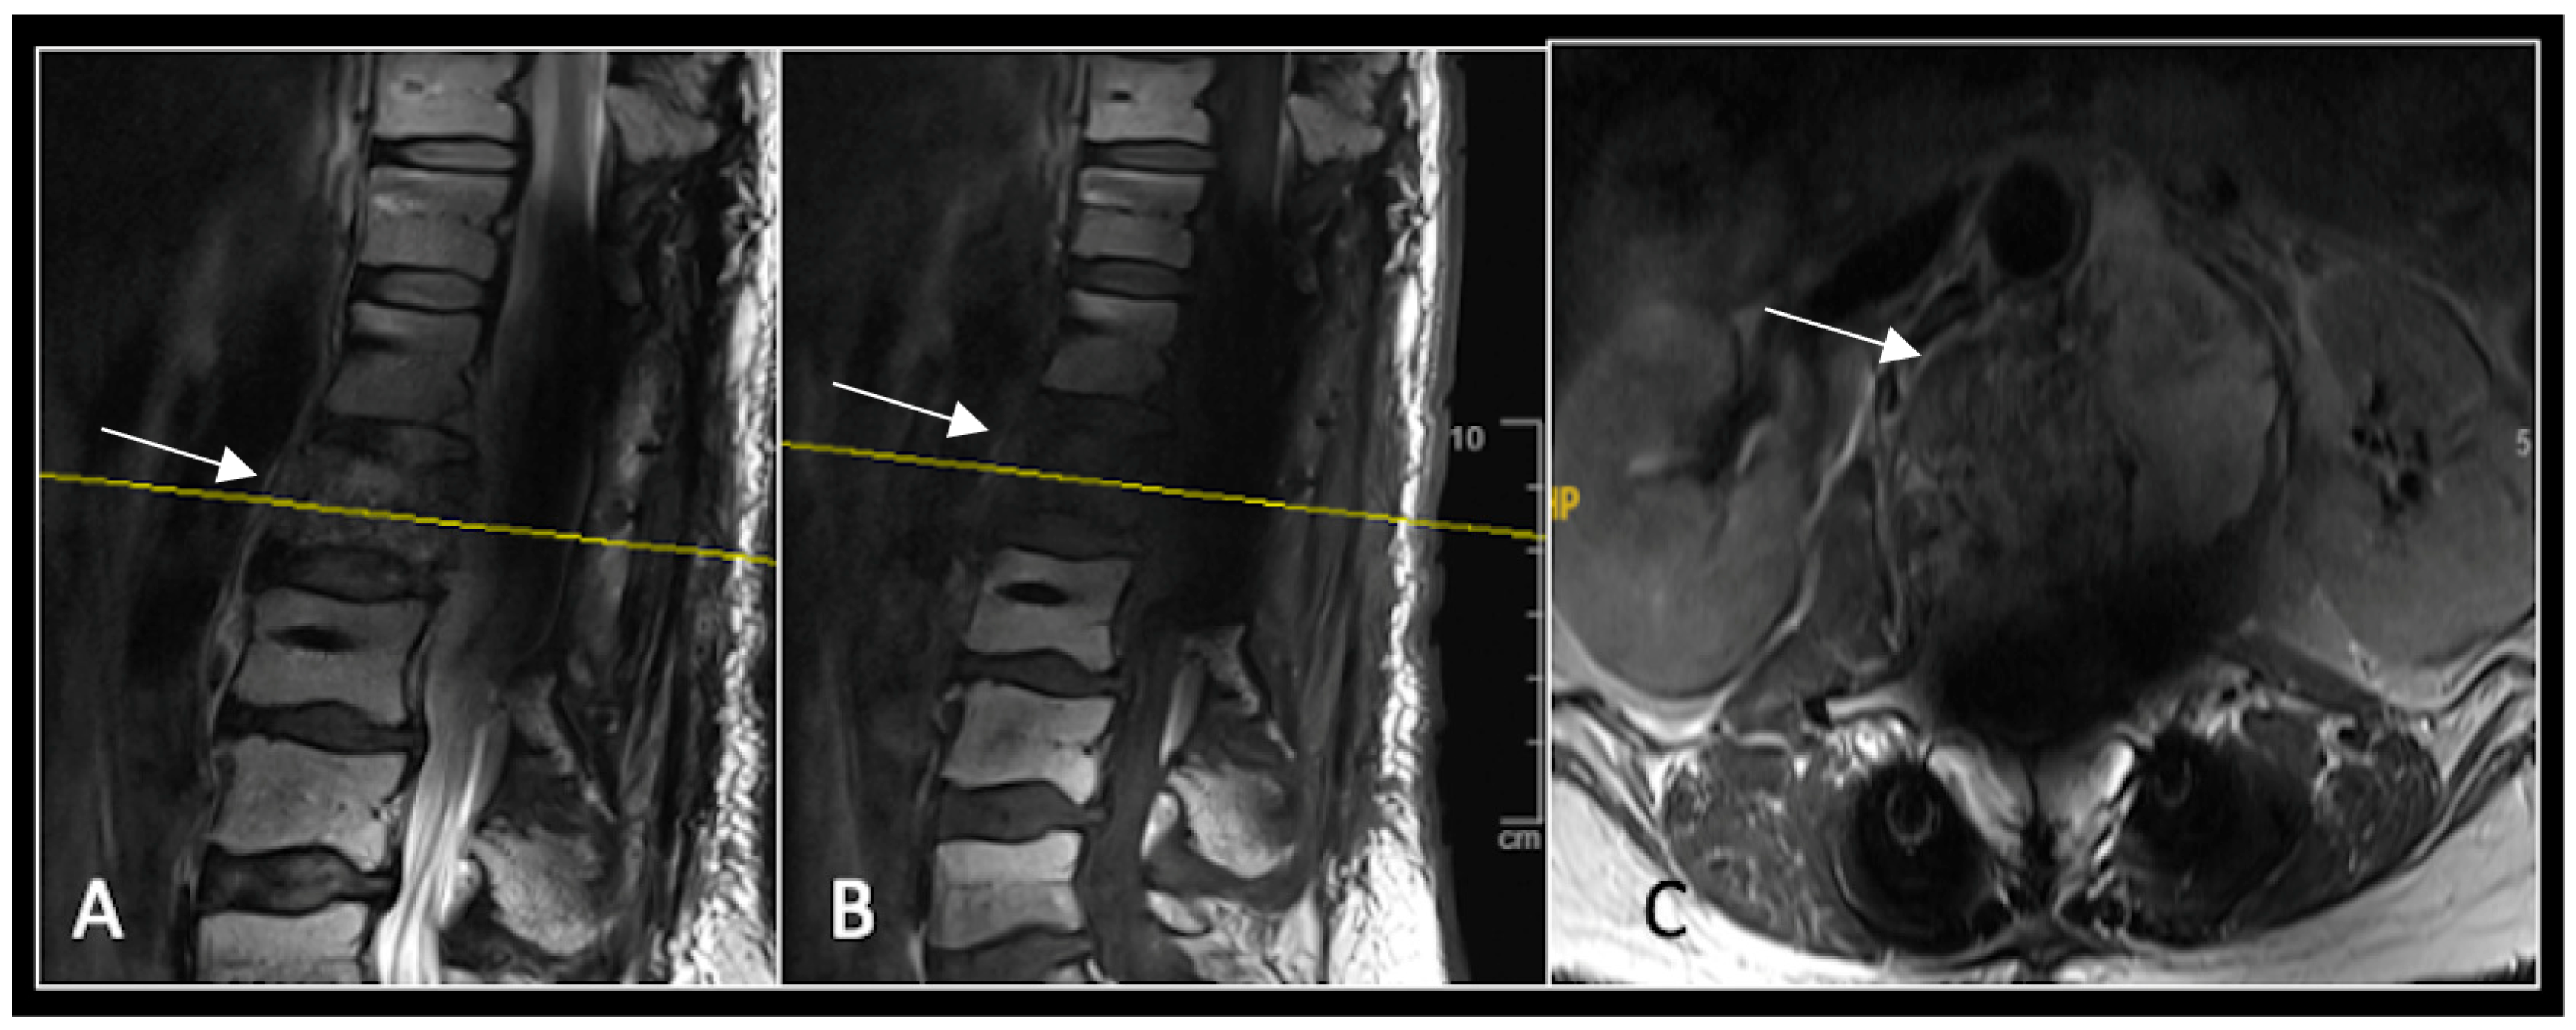

A 73-year-old male presented with an eight-month history of neck pain that was exacerbated on lying flat. He denied any symptoms of myelopathy and radiculopathy. He did not have any constitutional symptoms of malignancy. Past medical history included hypertension, renal cysts, and an ascending thoracic aneurysm. Examination was unremarkable. Diagnostic whole-spine MRI imaging demonstrated a large lobular mass localised to the cervical spine (Figure 2). Biopsy confirmed a conventional chordoma, and he underwent separation surgery followed by adjuvant proton beam therapy. Postoperative surveillance imaging at 12 months demonstrated stable disease (Figure 3).

Figure 2.

MRI demonstrating a destructive lobular lesion localised to the C2 vertebra (chordoma) (arrow). There is significant left-sided extension into the paravertebral tissues laterally and epidural space centrally with indentation of the cord. The yellow line on the sagittal images denotes the level at which the corresponding axial section was obtained. (A) T2-W sagittal; (B) T1W sagittal; (C) T2W axial.